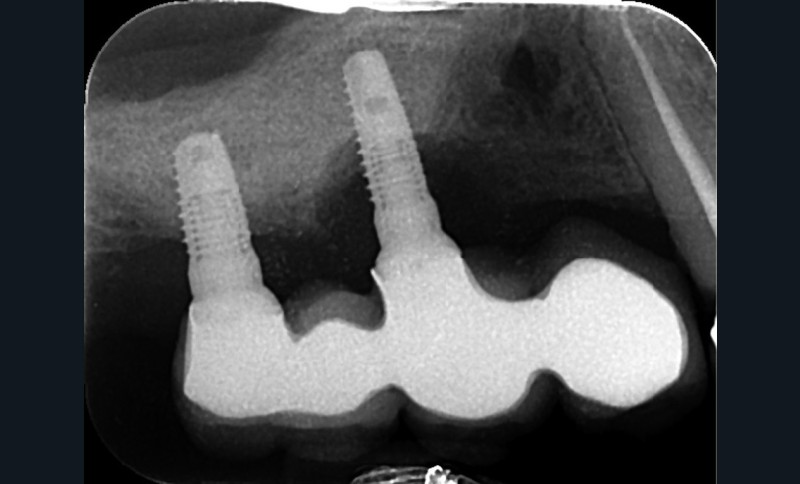

Le plus souvent pour des raisons carieuses et/ou parodontales l’avulsion d’une dent nécessite dans l’idéal son remplacement afin d’éviter une dégradation de l’appareil manducateur et des fonctions associées (mastication, phonation, sourire…).La mise en place d’implants dentaires ostéointégrés est une solution de choix pour remplacer les dents absentes car elle présente d’excellents résultats en termes de pérennité, de confort et d’esthétique. Ce n’est cependant pas une thérapeutique parfaitement fiable à 100 %. Dans un certain nombre de cas, des pertes osseuses péri implantaires se produisent, pouvant entraîner un inconfort, des douleurs et parfois la perte des implants.

Jemt [1] a listé de manière exhaustive les facteurs pouvant être responsables de la perte osseuse autour des implants (fig. 1). Il en a recensé au total 86. Cela montre bien l’origine plurifactorielle de ce type de pathologie. Il est difficile de traiter ici tous ces items ; cet article s’intéressera à deux grands types de facteurs de risques : l’hygiène bucco-dentaire (Jemt cite les antécédents de maladie parodontale, les causes de la perte des dents, le tartre, le biofilm, la plaque, le génotype et le phénotype bactérien) et la prothèse supra-implantaire (le design de l’infrastructure, son adaptation, son immobilité, le design de la prothèse sont également listés).